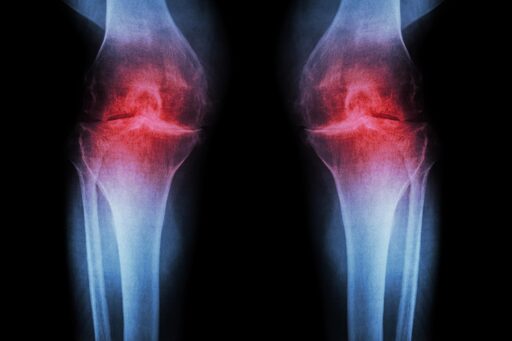

In mice (of course) and human tissue exvivo. Earlier phase 1 studies with 15-PGDH has shown that it is safe and active in healthy volunteers.